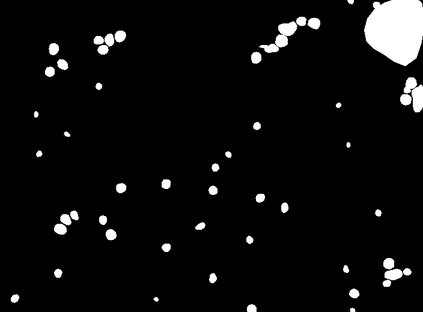

Bright-field microscopy, a cost-effective solution for live-cell culture, is often the only resource available, along with standard CPUs, for many low-budget labs. The inherent challenges of bright-field images -- their noisiness, low contrast, and dynamic morphology -- coupled with a lack of GPU resources and complex software interfaces, hinder the desired research output. This article presents a novel microscopy image analysis framework designed for low-budget labs equipped with a standard CPU desktop. The Python-based program enables cytometric analysis of live, unstained cells in culture through an advanced computer vision and machine learning pipeline. Crucially, the framework operates on label-free data, requiring no manually annotated training data or training phase. It is accessible via a user-friendly, cross-platform GUI that requires no programming skills, while also providing a scripting interface for programmatic control and integration by developers. The end-to-end workflow performs semantic and instance segmentation, feature extraction, analysis, evaluation, and automated report generation. Its modular architecture supports easy maintenance and flexible integration while supporting both single-image and batch processing. Validated on several unstained cell types from the public dataset of livecells, the framework demonstrates superior accuracy and reproducibility compared to contemporary tools like Cellpose and StarDist. Its competitive segmentation speed on a CPU-based platform highlights its significant potential for basic research and clinical applications -- particularly in cell transplantation for personalised medicine and muscle regeneration therapies. The access to the application is available for reproducibility